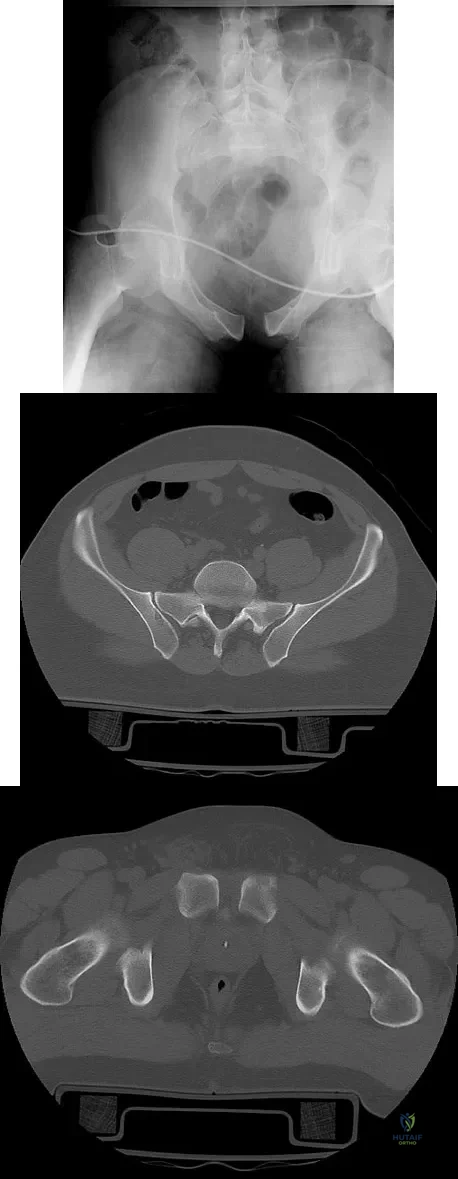

A 28-year-old cowgirl was injured while herding cattle 1 week ago. A radiograph and CT scans are shown in Figures 13a through 13c. What is the most appropriate management for this injury?